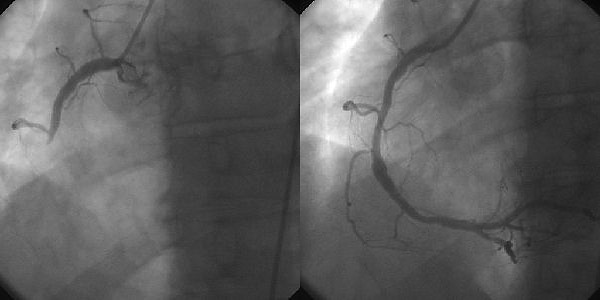

The first group is often due to a blockage in the heart arteries made up of an atherosclerotic plaque. This plaque gradually can narrow the blood vessel, but dangerously it can also crack, on top of which a blood clot forms (like in the picture below) and blocks off the entire vessel. It can also be due to the artery squeezing abnormally (vasospasm), or other factors such as low oxygen in the blood (hypoxia) or low blood levels (anaemia).

A STEMI is a critical emergency and the most dangerous type of problem – the blood supply is completely blocked, and the body cannot unblock it. Muscle cells will continue to die as long as the blockage (a mixture of thrombus and plaque) remains there. The patient either needs an urgent angiogram and stent, or if not available, a special clot busting medication called thrombolysis. In this type of heart attack, the full thickness of the heart muscle is at risk. In the picture below, you can see two pictures from an angiogram; on the right is how the vessel should look, and on the left it is completely blocked.